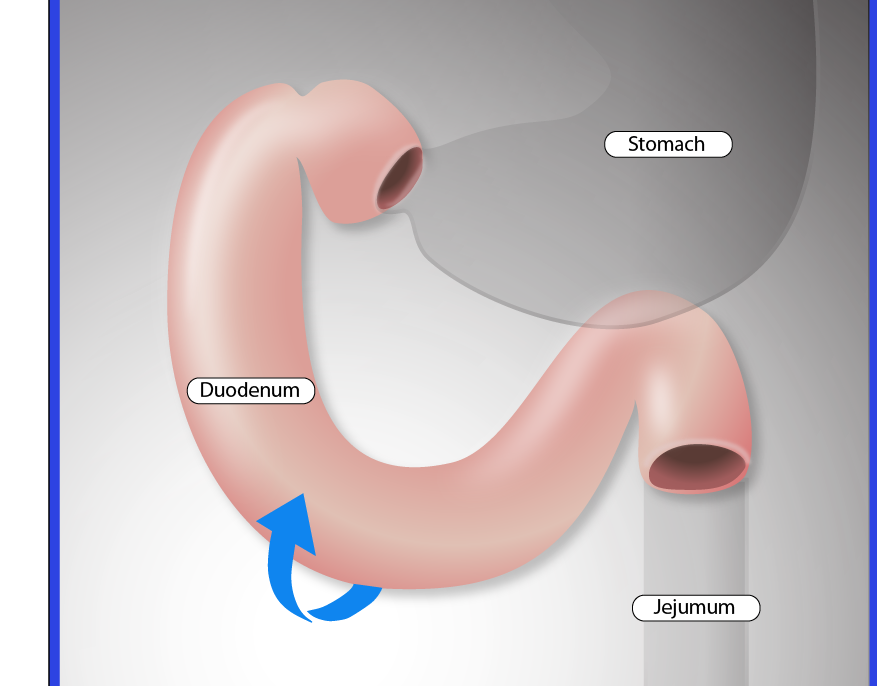

BioArt

Illustrating molecular method of action & drug delivery systems